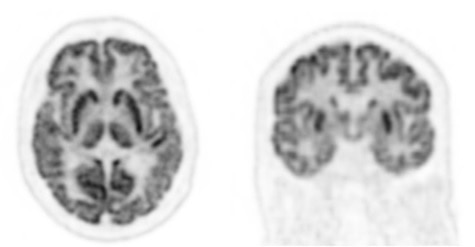

High resolution brain image demonstrating clear differentiation of grey and white matter, as well as separation of gyri and sulci, to aid in diagnosis of neurological disorders such as epilepsy foci, dementia and metastatic disease.

Data acquired on an equivalent technology - SIGNA PET/MR.